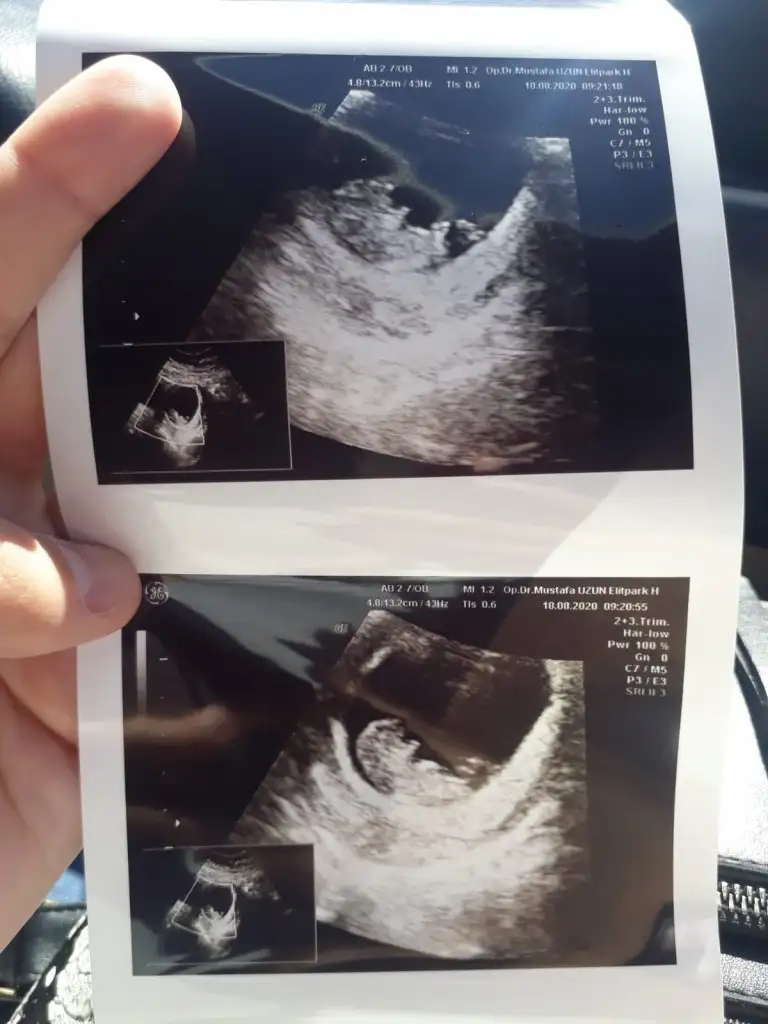

Canım ben anlamıyorum kendiminkini nubu nu ikra çizdiği halde usg demin bulamıyorum ikra ne yorum yaptıysa dogrudur

Tamam canımCanım ben anlamıyorum kendiminkini nubu nu ikra çizdiği halde usg demin bulamıyorum ikra ne yorum yaptıysa dogrudur

Sagol canm benim insallah saglıklı olsndaEvet erken zamanlarda yanilma payi oluyor.Ama nub erkek gibi gozukuyor.Insallah gonlunuzdeki olur